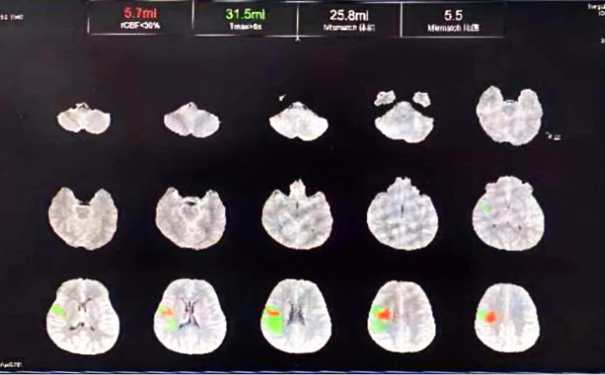

治疗前筛查CTP

OPTION研究是应用注射用重组TNK组织型纤溶酶原激活剂静脉溶栓治疗延长时间窗急性非大血管闭塞性卒中研究,它具有多中心、前瞻性、随机、开放标签、终点盲法研究,OPTION项目的技术方法、国内外的研究背景及创新性。目前对于发病4.5小时脑卒中的患者治疗,国内外都有成熟的指南共识;而对于4.5-24小时非大血管闭塞的脑卒中患者,目前国内外治疗的方法有限。随着影像技术的发展,目前可以识别卒中发作24小时内可挽救的缺血脑组织,而通过静脉溶栓实现再灌注有可能改善4.5-24小时内的临床预后。